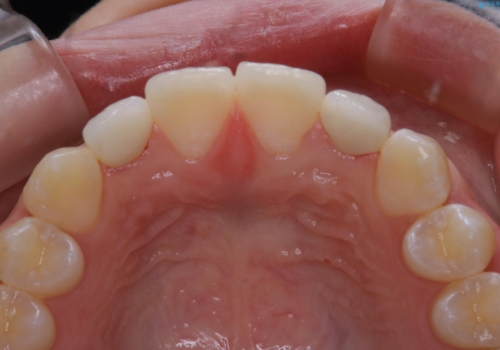

- 初診時、前歯部の見た目の改善を主訴にご来院されました。生まれつき歯が小さい状態の「矮小歯」とそれに伴う正中の「すきっ歯」があるため、大きなガタつきはないものの笑った時の印象に違和感が出る状態となっていました。

矮小歯が傾斜していることなどを踏まえ、より安全に治療を進めるために部分矯正を併用したセラミッククラウンでの治療を行うこととなりました。

今回のケースでは、歯が小さいだけでなく傾斜もしていたため補綴治療時に歯を削ることで神経の症状が出る可能性がありました。そのため、事前に部分矯正を行い歯軸の改善を行っておくことで、歯髄を温存することができました。